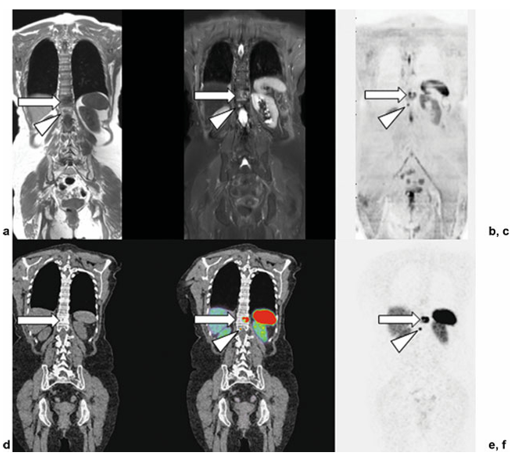

Hình 4. Hình ảnh cộng hưởng từ toàn thân đồng thời (WB-MRI) và chụp cắt lớp phát xạ positron/CT sử dụngoctreotide (PET/CT) ở một phụ nữ 73 tuổi với u thần kinh nội tiết phổi. (a–c) Hình ảnh T1 toàn thân, STIR, DWI cho thấy một ổ lớn (mũi tên) và một ổ nhỏ (đầu mũi tên) có cường độ tín hiệu thấp (SI) trên T1, cường độ tín hiệu trung gian trên STIR, và cản trở khuếch tán tại hai đốt sống ngực liền kề (T11 và T12).(d–f) Tương quan PET/CT với 68Ga-DOTATATE. Hình ảnh CT, PET/CT hợp nhất và PETcho thấy các tổn thương hoàn toàn tương ứng trong thân đốt sống T11 vàT12. Những tổn thương này là nguyên nhân gây xơ cứng xương mức độ nhẹ trên CT (hình d, mũi tên) và biểu hiện tăng bắt chất đánh dấu phóng xạ rõ rệt trên PET và PET/CT (hình e, f; mũi tên), qua đó chứng minh sự biểu hiện của thụ thể Somatostatin tại các ổ u.